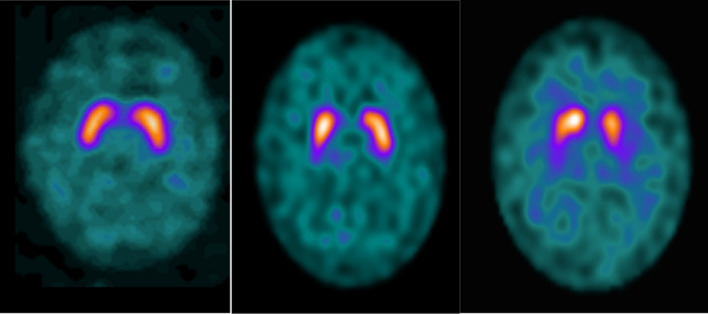

Aim: [123I]Ioflupane (DaTSCAN) has a high binding affinity to the dopamine (DA) transporter (DaT) and tenfold less affinity to serotonin (5-HT) transporter (SERT). Both neurotransmitters are considered to contribute to body weight regulation. This study assesses the association between body mass index (BMI) and DaTSCAN availability in brain.

Method: Scans from 74 consecutive patients who had undergone DaTSCAN single-photon emission computed tomography-computed tomography (SPECT-CT) were used to obtain semi- and absolute quantitative data in several volumes of interest (VOIs). Relative semi-quantitative specific binding ratios (SBRs) from Chang attenuated SPECT were obtained from GE DaTQUANT. Absolute normalised concentration (NC) was calculated from attenuation/scatter corrected SPECT-CT images, using an adapted version of the EARL Ltd (European Association of Nuclear Medicine (EANM) Research 4 Life) template. Scans were subdivided into either degenerative parkinsonism (abnormal = 49), borderline (n = 14) or scan without evidence of dopaminergic deficit (SWEDD = 11) using visual assessment and SBR values by two nuclear medicine consultants.

Results: SBRs did not correlate with BMI. However, NC values correlated negatively in the entire cohort, with the strongest correlation in the frontal (r = - 0.649. p = 0.000), occipital (r = - 0.555, p = 0.000) regions and pons (r = - 0.555, p = 0.000). In the abnormal (n = 49) and SWEDD group (n = 11), NC of the frontal region was the most correlated with BMI (r = - 0.570, p = 0.000; r = - 0.813, p = 0.002, respectively). In the borderline group (n = 14), the left posterior putamen displayed the strongest correlation (r = - 0.765, p = 0.001).

Conclusion: Absolute NC values demonstrate a strong inverse correlation with BMI, strongest in the extrastriatal regions. Due to the predominately non-overlapping distribution of DaT and SERT, this study suggests greater involvement of SERT in obesity with possible interplay with DA transmission.